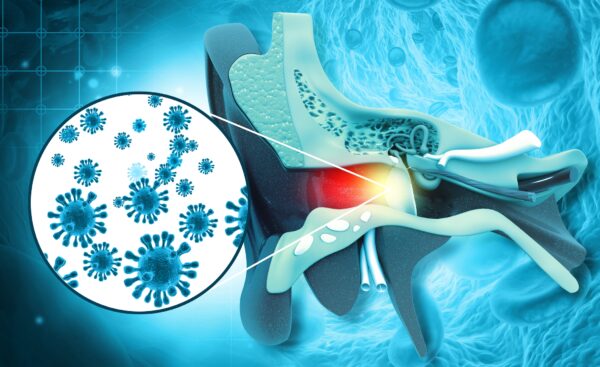

- Viêm ống tai ngoài là loại nhiễm trùng phổ biến nhất ở người lớn, không nên nhầm lẫn bệnh này với viêm tai giữa, vốn là loại nhiễm trùng tai phổ biến ở trẻ em.

- Đau, viêm, đóng vảy và chảy nước đều là các triệu chứng của viêm ống tai ngoài, nguyên nhân thường gặp nhất là do nước trong bể bơi, bồn tắm, công viên nước, đài phun nước, hồ, sông hoặc đại dương bị ô nhiễm.

Thông thường nước sẽ tự chảy ra ngoài, nhưng nếu không thoát được, nước có thể bị ứ lại và dẫn đến tình trạng viêm ống tai ngoài. Ban đầu, bạn có cảm giác không thoải mái – cảm giác hơi nhột nhột, đau đến chảy nước mắt ở mọi nơi từ tai đến xương hàm và cổ họng, đồng thời có thể nghe không rõ âm thanh.

Trong thực tế, các bác sĩ khuyên những người tham gia các môn thể thao dưới nước (hoặc thường xuyên ở dưới nước vì bất kỳ lý do nào khác) nên đeo nút bịt tai. Nhiễm trùng là điều cần phải cảnh giác nhất để phòng ngừa. Nhất là đối với nước nước hồ hoặc sông, hoặc từ nơi có thể bị ô nhiễm. Vi khuẩn có hại trong nước có thể gây viêm ống tai ngoài.

Theo American Academy of Otolaryngology—Head and Neck Surgery (Viện Tai mũi họng Hoa Kỳ – Phẫu thuật Đầu và Cổ), nguy cơ phát triển bệnh viêm ống tai ngoài tăng lên nếu bạn bị bệnh chàm, bệnh vẩy nến hoặc chứng rối loạn da mạn tính tương tự. Các tình trạng khác cũng khiến viêm ống tai ngoài trở nên phổ biến hơn, theo Medical News Today.

Trung tâm Kiểm soát và Phòng ngừa Dịch bệnh cho biết vi trùng có thể lây lan ngay cả qua màn sương mỏng của nước bị ô nhiễm trong bể bơi, hơi nước trong bồn tắm nước nóng, công viên nước, khu vui chơi dưới nước, đài phun nước tương tác, hồ, sông hoặc đại dương. Cụ thể hơn:

“Nhiễm trùng tai có thể xảy ra do để nước nhiễm bẩn đi vào tai sau khi bơi. Nhiễm trùng này, được gọi là bệnh tai của những người bơi lội hoặc bệnh viêm tai ngoài, không giống như bệnh viêm tai giữa thông thường ở trẻ em.”

“Nhiễm trùng xảy ra ở ống tai ngoài và có thể gây đau đớn, khó chịu cho người bơi lội ở mọi lứa tuổi. Tại Hoa Kỳ, bệnh viêm ống tai ngoài là nguyên nhân của khoảng 2.4 triệu lượt khám bệnh mỗi năm và tiêu tốn gần nửa tỷ USD chi phí chăm sóc sức khỏe.”

Ngoài đau, đỏ, và sưng bên trong và bên ngoài tai, các triệu chứng mà Medical News Today liệt kê bao gồm:

- Mất thính giác một phần (và tạm thời) do sưng tấy.

- Da có vảy, bong tróc bên trong và xung quanh ống tai.

- Chảy nước hoặc mủ có thể có mùi hôi.

- Ngứa và kích ứng bên trong và xung quanh ống tai.

- Đau tai khi cử động miệng để nói hoặc ăn.

- Sưng các tuyến bạch huyết trong cổ họng.

Theo Học viện Bác sĩ Gia đình Hoa Kỳ (AAFP), bệnh viêm ống tai ngoài liên quan đến tình trạng viêm bên ngoài ống tai và có thể lan đến màng nhĩ:

“Dạng cấp tính có tỷ lệ mắc bệnh hàng năm khoảng 1% và tỷ lệ mắc bệnh suốt đời là 10%. Trong một số trường hợp hiếm gặp, nhiễm trùng xâm lấn mô mềm và xương xung quanh; trường hợp này được gọi là viêm ống tai ngoài ác tính (hoại tử) và là một trường hợp cấp cứu y tế xảy ra chủ yếu ở những bệnh nhân đái tháo đường lớn tuổi.”

Medical News Today nhắc lại rằng nhiễm trùng nặng có thể dẫn đến sốt và đau ở mặt, cổ, hoặc một bên đầu. Ngoài ra:

“Các biến chứng của viêm ống tai ngoài có thể bao gồm khó nghe và đau tạm thời. Các biến chứng hiếm gặp bao gồm nhiễm trùng lâu dài, nhiễm trùng mô sâu, tổn thương xương và sụn, nhiễm trùng lan đến não hoặc dây thần kinh.”

Bệnh viêm ống tai ngoài là bệnh nhiễm trùng phổ biến nhất mà người bơi lội gặp phải và có thể kéo dài tới ba tuần. Nếu tình trạng này kéo dài hơn hoặc tình trạng đau và viêm kéo dài trong vài ngày thì bạn nên đi khám ở các chuyên gia y tế.